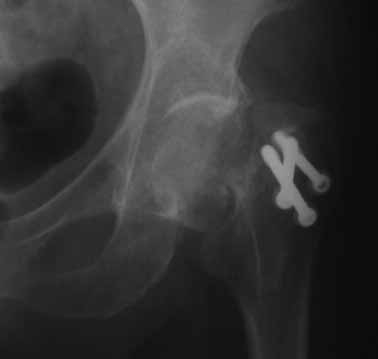

На консультации вот такие снимки. Больная 72 года. упала в быту 26 декабря 2010г.

Оперирована 30 декабря 2010г. в одном из стационаров края. Назначили дополнительное обследование, а пока хотелось-бы услышать мнение по-поводу возможностей сохранения головки. Больная из льготного контингента, т.е. современные констукции и эндопротез маловероятны.

Обычное после фиксации перелома шейки варусное смещение по разным публикациям встречается от 15-24%. В оценке состояния пожилых больных применяется коэффициент (ADL) Activities of daily living. В зависимости от базового ADL, т.е. до переломного состояния планируется лечение. Кроме того, возраст играет важную роль, и не всегда функциональное состояние совпадает с истинным возрастом. Поэтому каждый случай после 60 лет рассматривается отдельно.

Показанием к органосохраняющей вальгусной остеотомии является более молодой возраст. Более пожилым, тем более в 72 г., можно ограничиться дешевым цементным эндогемипротезом. Биполярные эндопротезы приводят к удорожанию операции, и нет данных, что они функционируют лучше. Компоненты головки замыкаются друг в друге после первых вращений, и действует как одно целое.